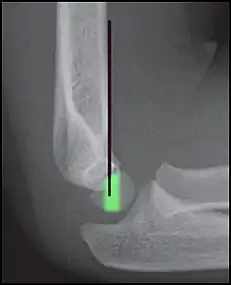

Anterior humeral line (black line), with normal area passed on the capitulum of the humerus colored in green in a 4 year old child.[9]

The anterior humeral line is not reliable in children with sparse ossification of the capitulum, such as in this 6 months old child.[9]